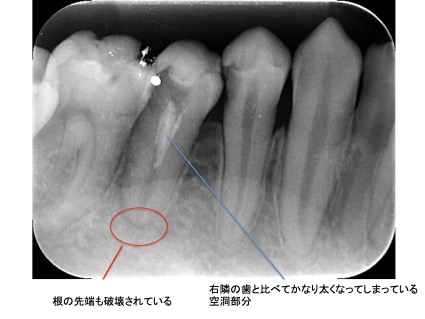

それは歯の先に枝分かれが多く存在し、そこにばい菌が入り込んで難治性となっているからです。ではその場合どうするのか?外科治療をします。その枝分かれの部分を切り落とすのです。今回はその前後のレントゲンの写真をお見せします。

| 根の中の薬が十分に充填されておらず、根の先が周りと比べて黒くなっており、炎症があると判断できます。 | 根の中にしっかりとお薬を緊密に充填しましたが、まだ根の先に黒くなっている部分があります。 |